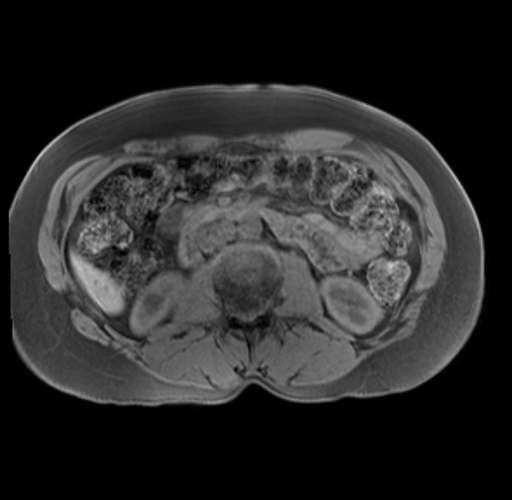

Imaging Analysis

Look through the patient's CT scan to identify any areas of concern for the necessary procedure.

Based on your CT findings, which issue(s) are present and would give reason for "planned slowing down moment(s)" in this case?

Considering a standard distal pancreatectomy procedure, what step(s) of the operation would you do differently in this case?